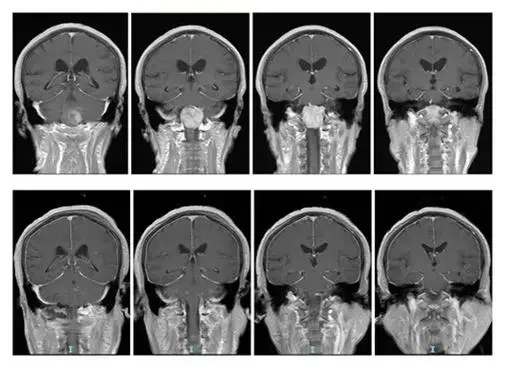

脑膜瘤的诊断依靠临床症状、影像学检查及病理学检查。常见的影像学检查包括CT(计算机断层扫描)和MRI(磁共振成像)。这些检查可以显示肿瘤的大小、位置以及对周围结构的压迫情况。